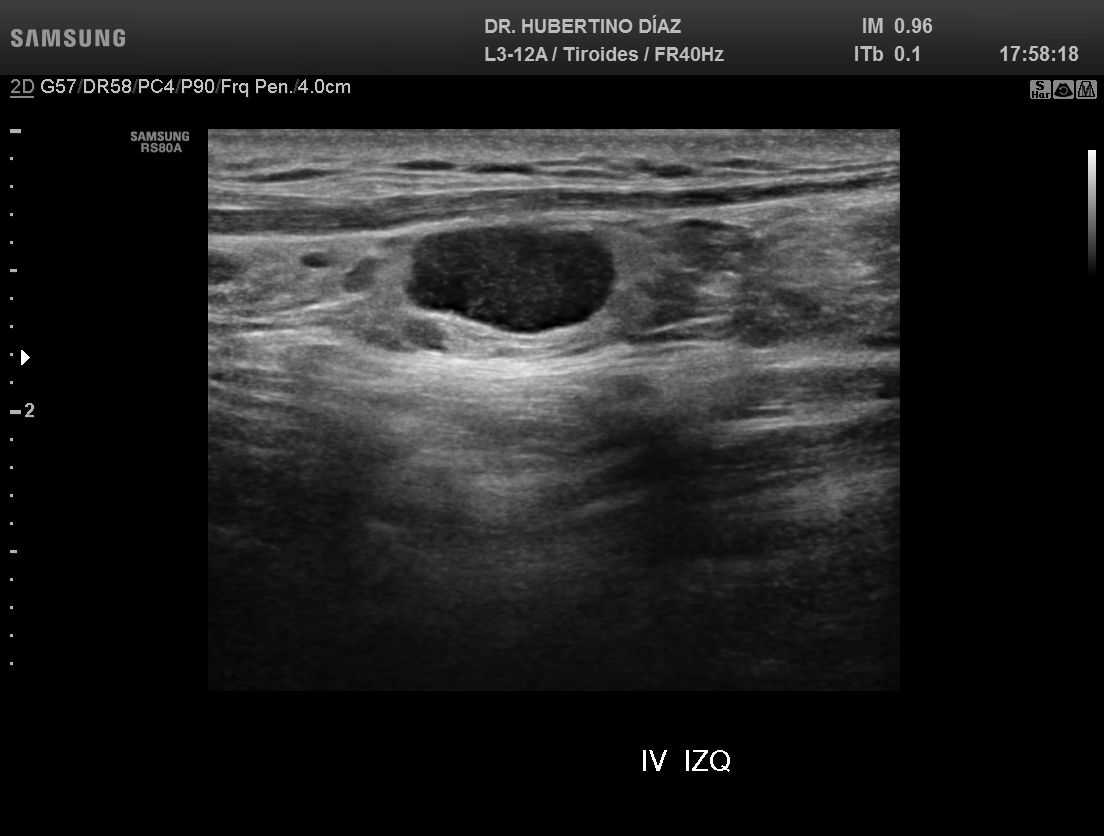

ECOGRAFÍA DE CUELLO - CERVICAL

El objetivo final en el estudio de nódulo tiroideo es determ...